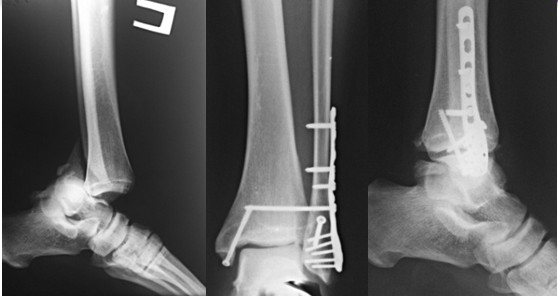

Остеосинтез обеих лодыжек правой голени пластинами